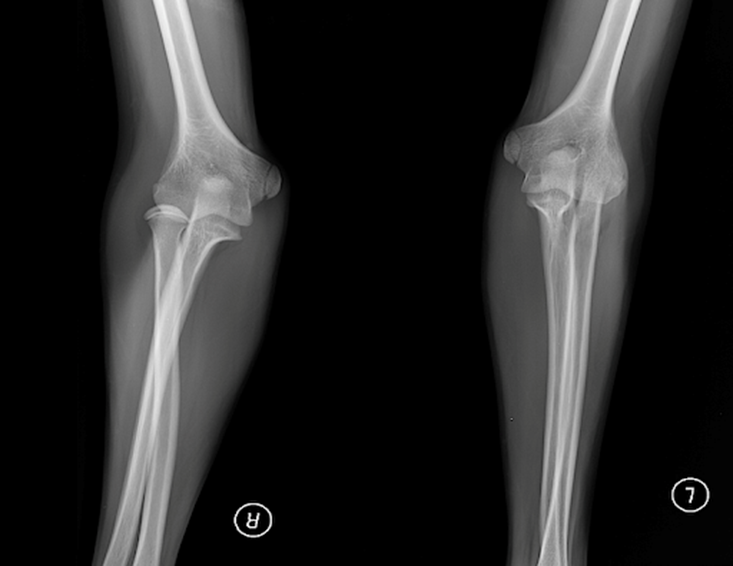

РОЗПІЗНАЙТЕ КІСТКУ. ПЕРЕЛОМ ЯКОЇ ЇЇ ЧАСТИНИ ВИ БАЧИТЕ НА РЕНТГЕНОГРАМІ?

варіанти відповідей

ULNA

RADIUS

FEMUR, ШИЙКА

ПРОКСИМАЛЬНОГО ЕПІФІЗА

ДИСТАЛЬНОГО ЕПІФІЗА

ДІАФІЗА

ЛІКТЬОВОГО ВІДРОСТКА

ПРОМЕНЕВОГО ВІДРОСТКА